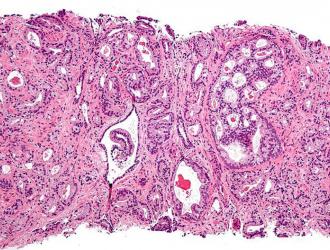

La terapia “chemio-free”, con l'aggiunta della molecola abiraterone al trattamento ormonale standard, si conferma efficace nel mantenere stabile la malattia, e quindi allungare la sopravvivenza dei pazienti con tumore alla prostata metastatico alla diagnosi e ad alto rischio,...